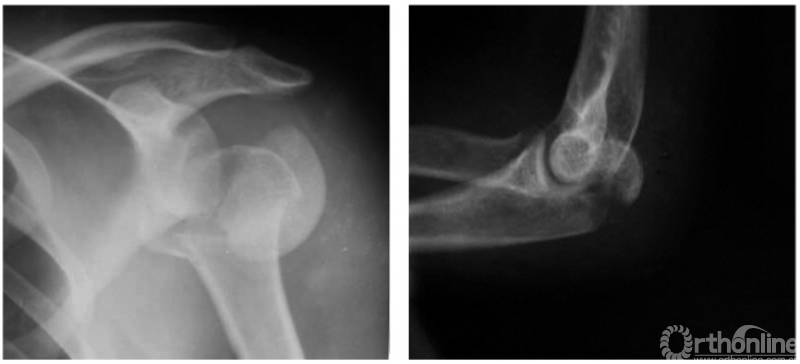

例2:希-萨(Hill-Sachs)二氏损伤。肱骨头后外侧劈裂骨折形成楔形缺损,骨折块下移并肩关节喙突下脱位(如下图)。

例2:肩关节向外旋转性脱位并肱骨解剖颈碎折及同侧尺骨鹰嘴骨折(如下图)。